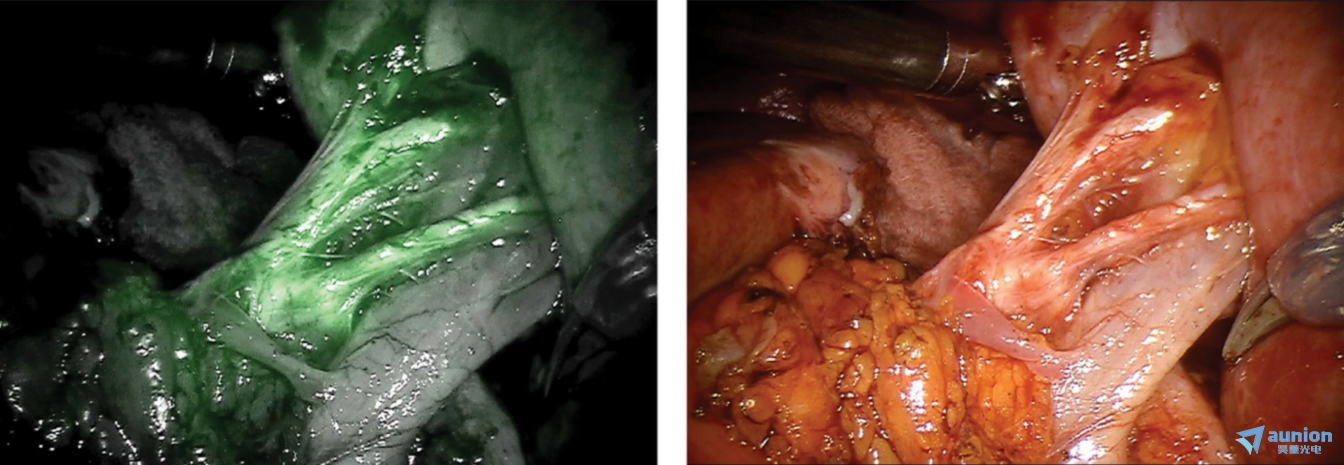

| 机器人辅助微创肾部分切除术期间肾门区域的白光反射图像 | 机器人辅助微创肾部分切除术期间肾门血管的近红外荧光图像 |

近红外激发用于增强血管可视化和经 FDA 批准的荧光物质

在手术或介入内窥镜检查过程中,肿瘤通常靠视觉检查和触诊来判断的。然而,肿瘤组织有时与健康组织难分彼此,导致在多达 40% 的手术病例中切除不净。这不仅影响患者预后,也带来额外的经济负担。将高灵敏度成像系统与肿瘤靶向成像剂相结合,在手术或介入过程中实时可视化肿瘤,让医生看得更清、切得更准,从而显著提高检出率和切除准确性。